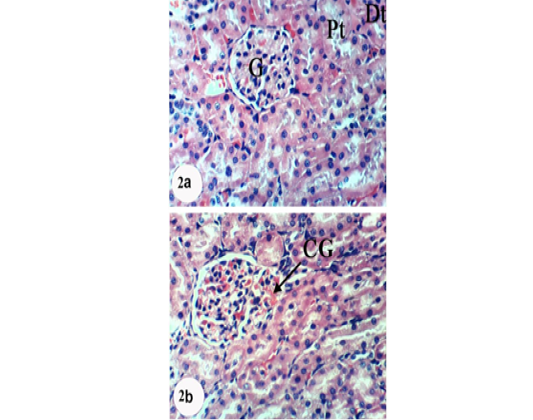

Photomicrographs of H&E stained kidney sections of APAP-administered rats treated with navel orange peel hydroethanolic extract. 2a: Photomicrograph of kidney section showing slight congestion of glomerulus (CG). 2b: Photomicrograph of kidney section showing normal structure of kidney; normal glomerulus (G), proximal (Pt) and distal tubules (Dt). X400